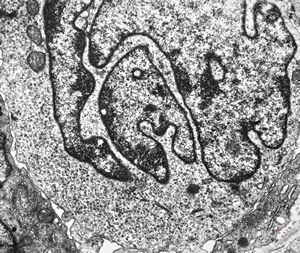

F, 57y. | mycosis fungoides … cerebriform nucleus of Sézary cell